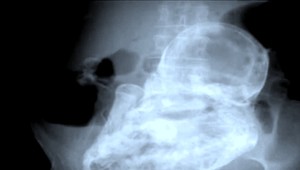

Bez ultrazvuku a konzultácií so špecialistom sa táto anomália nedá odhaliť, pretože pseudogravidita prebieha rovnako, ako keď v tele matky skutočne rastie dieťa. "Takýmto ženám sa môže zväčšiť bruško," dodáva Petrenko.